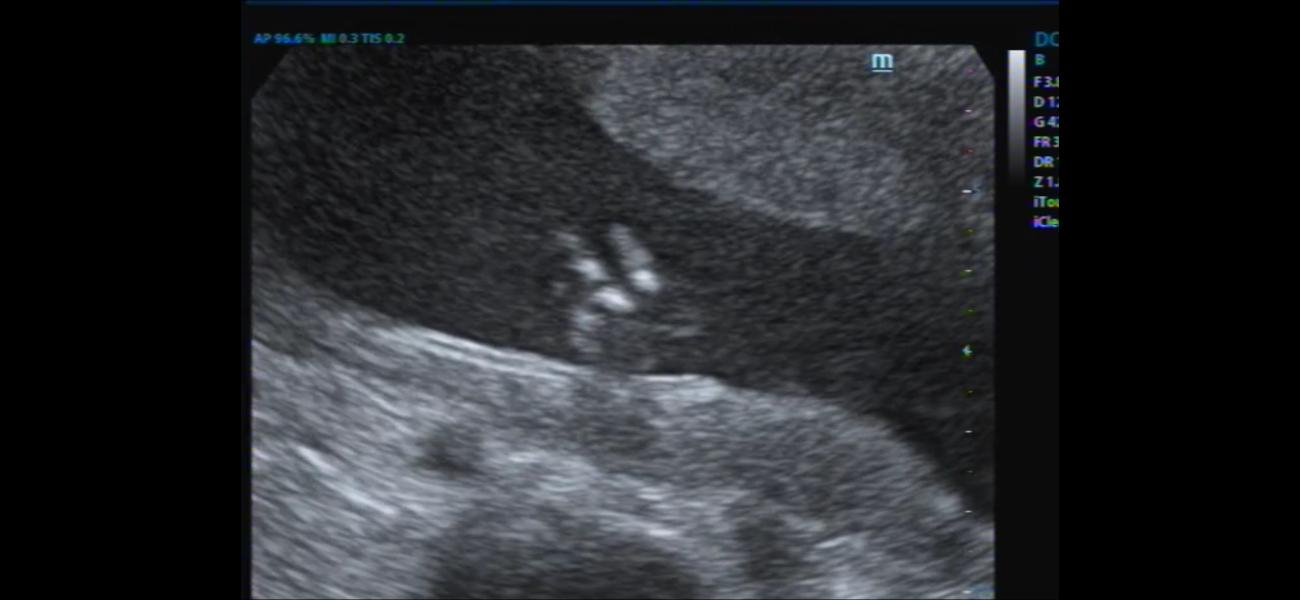

Девочки,сделала скрин из видео со 2 скрининга ( бесплатного ) , там где врач не увидел фаланг на мизинце.

Что скажете ?

Вправду не видно , или я себе накручиваю,что он есть?☹️